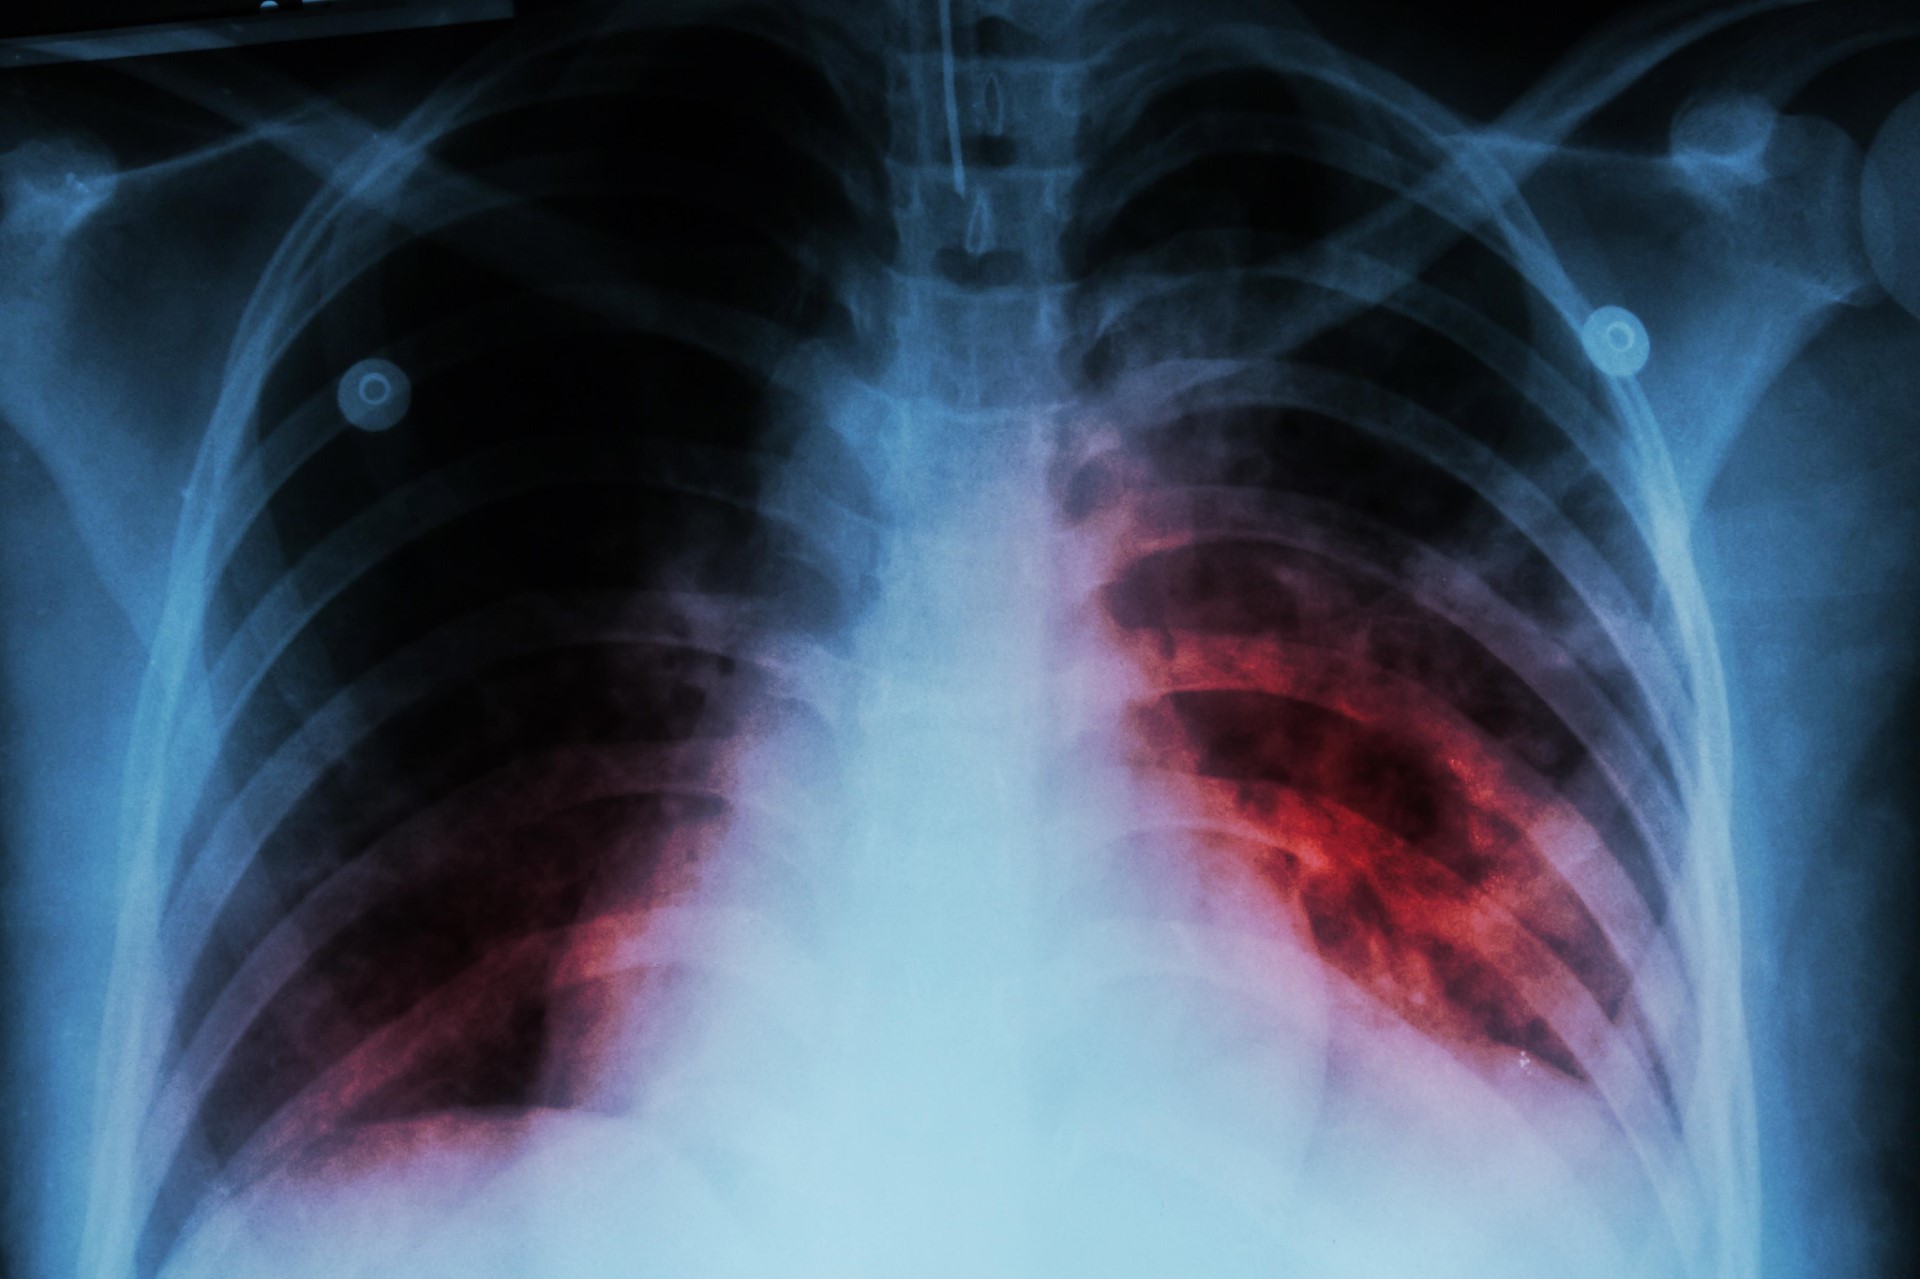

ئه‌مڕۆ 24-3، رۆژی جیهانی سیله‌ كه‌ یه‌كێكه‌ له‌نه‌خۆشییه به‌كتریاییه‌‌ بڵاوه‌كان له‌جیهاندا، به‌ڵام ده‌كرێت رێی لێبگیرێت و پاش توشبونیش چاره‌سه‌ری هه‌یه‌. ئه‌مانه‌ی خواره‌وه‌ چه‌ند زانیارییه‌كی سه‌رنجڕاكێشن سه‌باره‌ت به‌م نه‌خۆشییه‌: